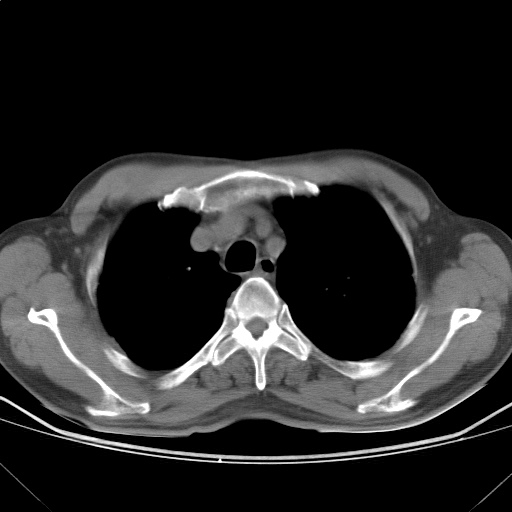

以下是引用随光逐影在2009-5-1 13:53:00的发言:[br]考虑为:1)两肺血行播散型肺结核;2)右肺下叶炎症感染。3)右侧胸膜增厚。